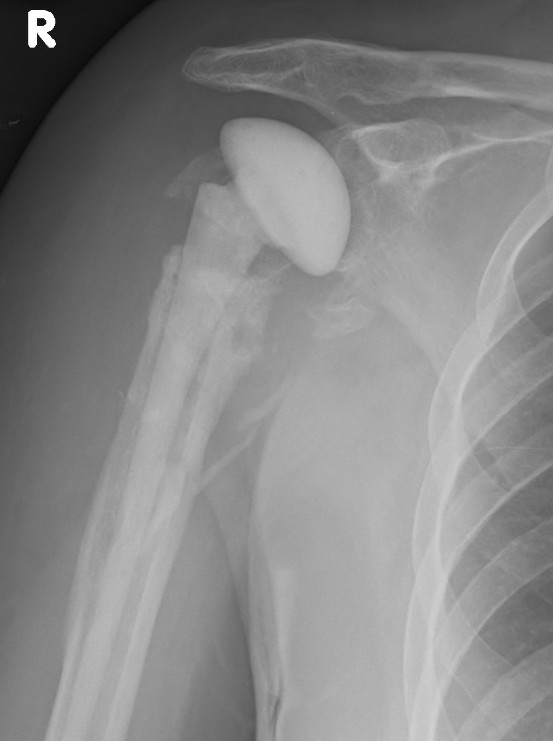

TSR Anterior Instability LateralTSR Anterior Instability AP